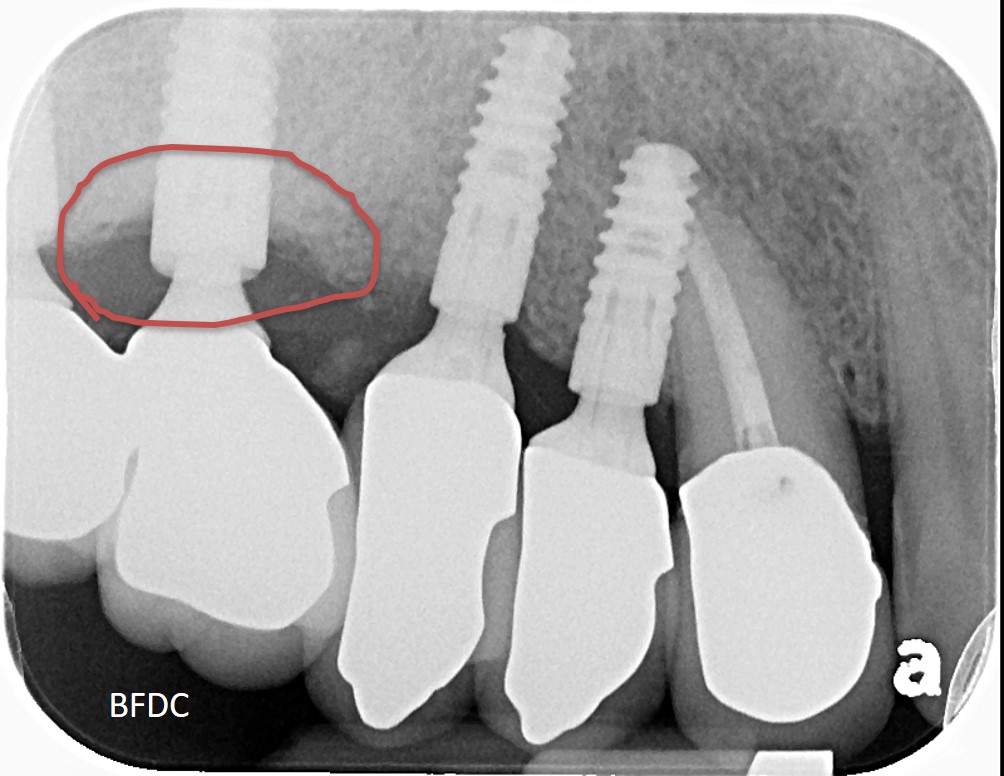

5年前,植牙剛完成,術後X光,骨癒合良好

5年後追蹤,植體周圍骨破壞